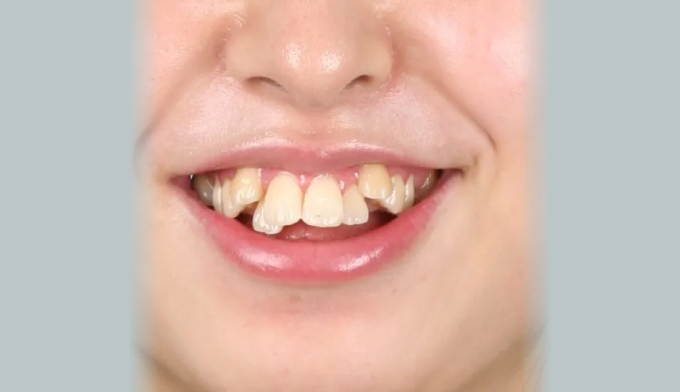

덧니,

돌출입,

개방교합

덧니를 해소하기 위해 필요한 공간의 양도 매우 많으며, 돌출의 정도도 심한편입니다. 또한 개방교합도 존재하고 있으며, 악궁의 폭도 매우 좁은편입니다.

25개월의 교정기간동안 덧니,돌출입, 그리고 개방교합을 해소하였습니다.